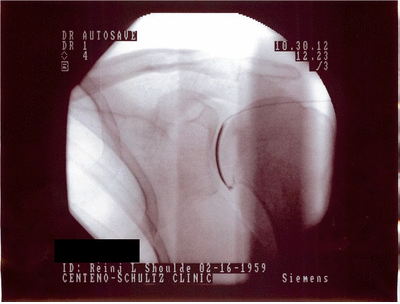

Home General Intra articular Injection of Your Own Stem Cells 9 years ago 9 years ago General, Surgery Intra articular Injection of Your Own Stem Cells by samer176 9 years ago9 years ago 41views [zombify_post] Post PaginationPrevious PostPreviousNext PostNext gif, injection, intra articular, shoulder joint